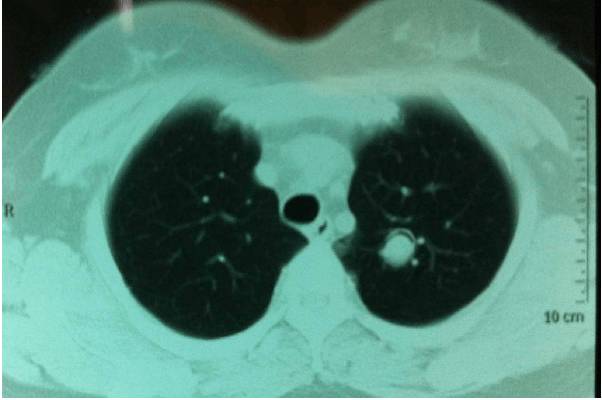

6.空洞腔内容物:气液平面主要见于急性肺脓肿。一般认为肺结核空洞无气液面,但有的研究指出,气液面在肺结核空洞占9%~21%,多为合并感染及出血。空洞内的固体成分为肿瘤结节、干酪坏死物、凝血块和霉菌球等,在空洞内气体的衬托下使空洞表现为不同的形态。霉菌球发生于肺癌、肺结核及慢性肺脓肿空洞,或支气管扩张、肺囊肿内,为类圆形可移动的结节,多位于坠积部位。新月形空洞为弓形的气体影,总是位于霉菌球的上方。若空洞内容物与洞壁附着,如侵袭性笰状菌病、肺癌、肺结核空洞,新月形的气体影可位于空洞的侧方或下方。如空洞内容物与空洞的前壁或后壁附着,在后前位投影形成“ 靶样征”。有的固态内容物位于液体之上形成“水上浮萍征”,见于细粒棘球蚴囊肿的内膜破裂后,此症属于空腔病变,应当与空洞病变鉴别。

7.增强表现:一般用于2cm~3cm大小的厚壁空洞病变的鉴别诊断。肺结核的纤维干酪空洞的洞壁不强化或外周有薄层强化,肺癌空洞的壁大部强化。